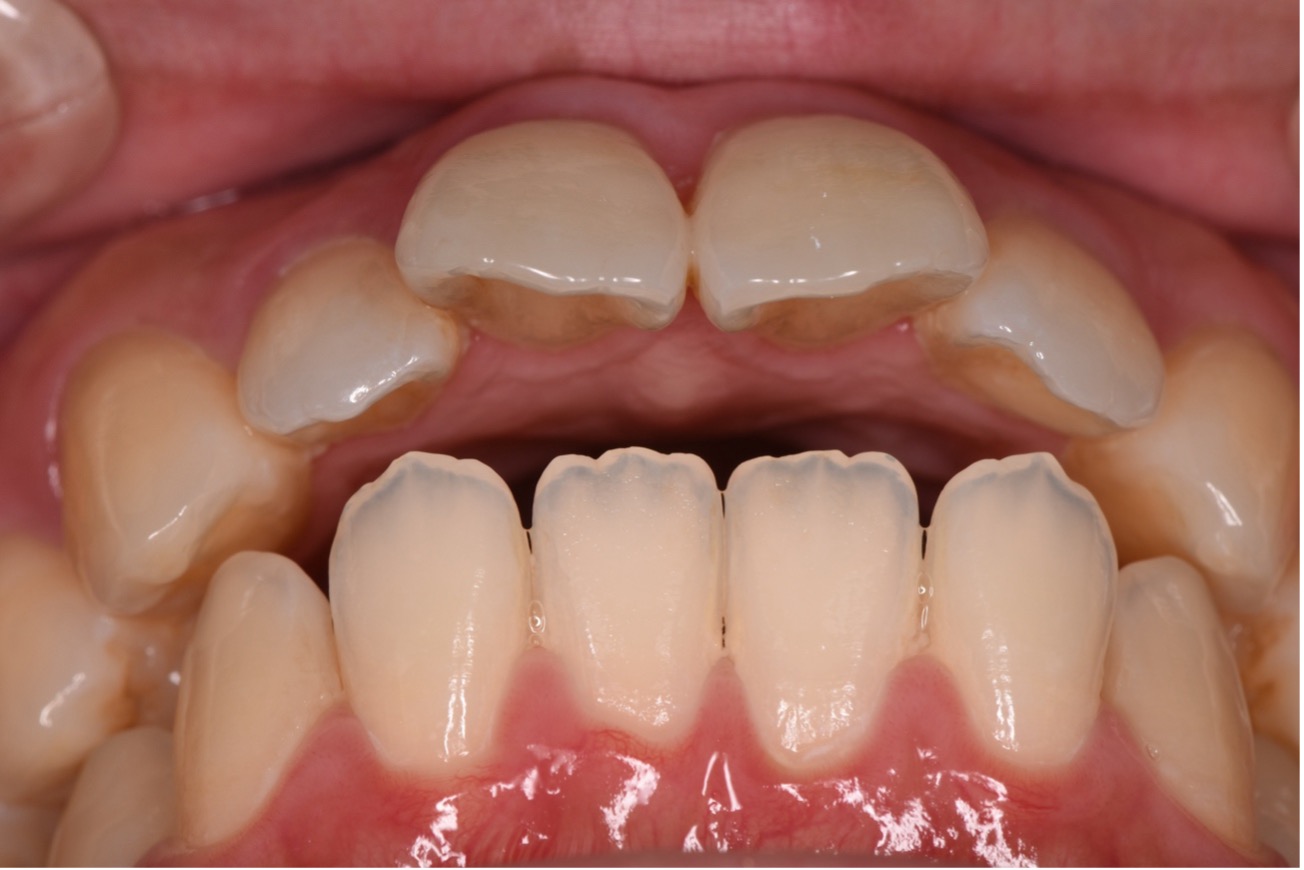

下の歯が上の歯よりも前に出ている状態です。

顎関節への負担や全身のバランスが悪くなる場合があり、お子様の場合は咀嚼が不十分になることで体の発育にも影響する可能性もあります。

よく噛むことは食べ物の消化のしやすさにも直結し、全身の健康にも影響します。

矯正治療で噛み合わせを整えることは、食事のしやすさの改善にも繋がります。